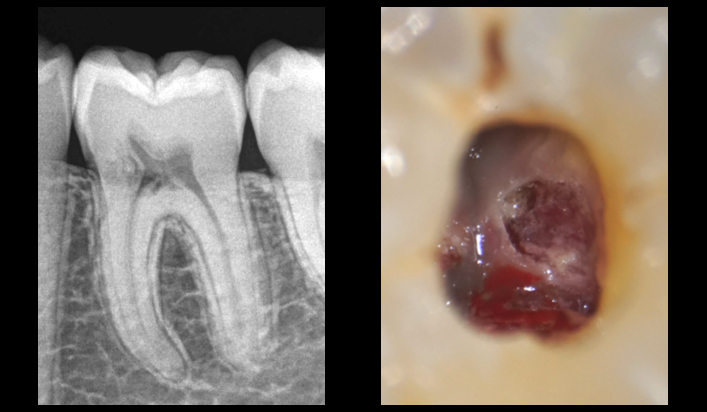

❓ 𝐏𝐨𝐮𝐫𝐪𝐮𝐨𝐢 𝐥’𝐎𝐃𝐅 𝐩𝐨𝐮𝐫𝐫𝐚𝐢𝐭 𝐞̂𝐭𝐫𝐞 𝐮𝐧 𝐟𝐚𝐜𝐭𝐞𝐮𝐫 𝐝𝐞 𝐫𝐢𝐬𝐪𝐮𝐞 𝐝𝐞𝐬 𝐫𝐞́𝐬𝐨𝐫𝐩𝐭𝐢𝐨𝐧𝐬 𝐫𝐚𝐝𝐢𝐜𝐮𝐥𝐚𝐢𝐫𝐞𝐬 𝐞𝐱𝐭𝐞𝐫𝐧𝐞𝐬 𝐜𝐞𝐫𝐯𝐢𝐜𝐚𝐥𝐞𝐬 ? 🦷

📚 L’hypothèse émise dans la littérature est que 𝐥’𝐮𝐭𝐢𝐥𝐢𝐬𝐚𝐭𝐢𝐨𝐧 𝐝𝐞 𝐟𝐨𝐫𝐜𝐞𝐬 𝐨𝐫𝐭𝐡𝐨𝐝𝐨𝐧𝐭𝐢𝐪𝐮𝐞𝐬 𝐢𝐦𝐩𝐨𝐫𝐭𝐚𝐧𝐭𝐞𝐬 pourrait causer une 𝐧𝐞́𝐜𝐫𝐨𝐬𝐞 𝐭𝐢𝐬𝐬𝐮𝐥𝐚𝐢𝐫𝐞, impliquant une 𝐝𝐢𝐟𝐟𝐞́𝐫𝐞𝐧𝐜𝐢𝐚𝐭𝐢𝐨𝐧 𝐞𝐧 𝐨𝐝𝐨𝐧𝐭𝐨𝐜𝐥𝐚𝐬𝐭𝐞𝐬, résorbant ainsi la dentine exposée.